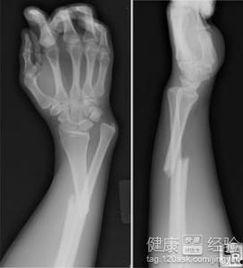

胳膊肘骨折了,这可真是个让人头疼的小麻烦。不过别担心,今天我就要给你带来一份超级详细的胳膊肘骨折康复训练正确视频攻略,让你在家也能轻松恢复,重拾活力!

胳膊肘骨折可不是闹着玩的,恢复得慢了,不仅会影响日常生活,还可能留下后遗症。所以,正确的康复训练至关重要。下面,我们就来看看有哪些训练方法吧!